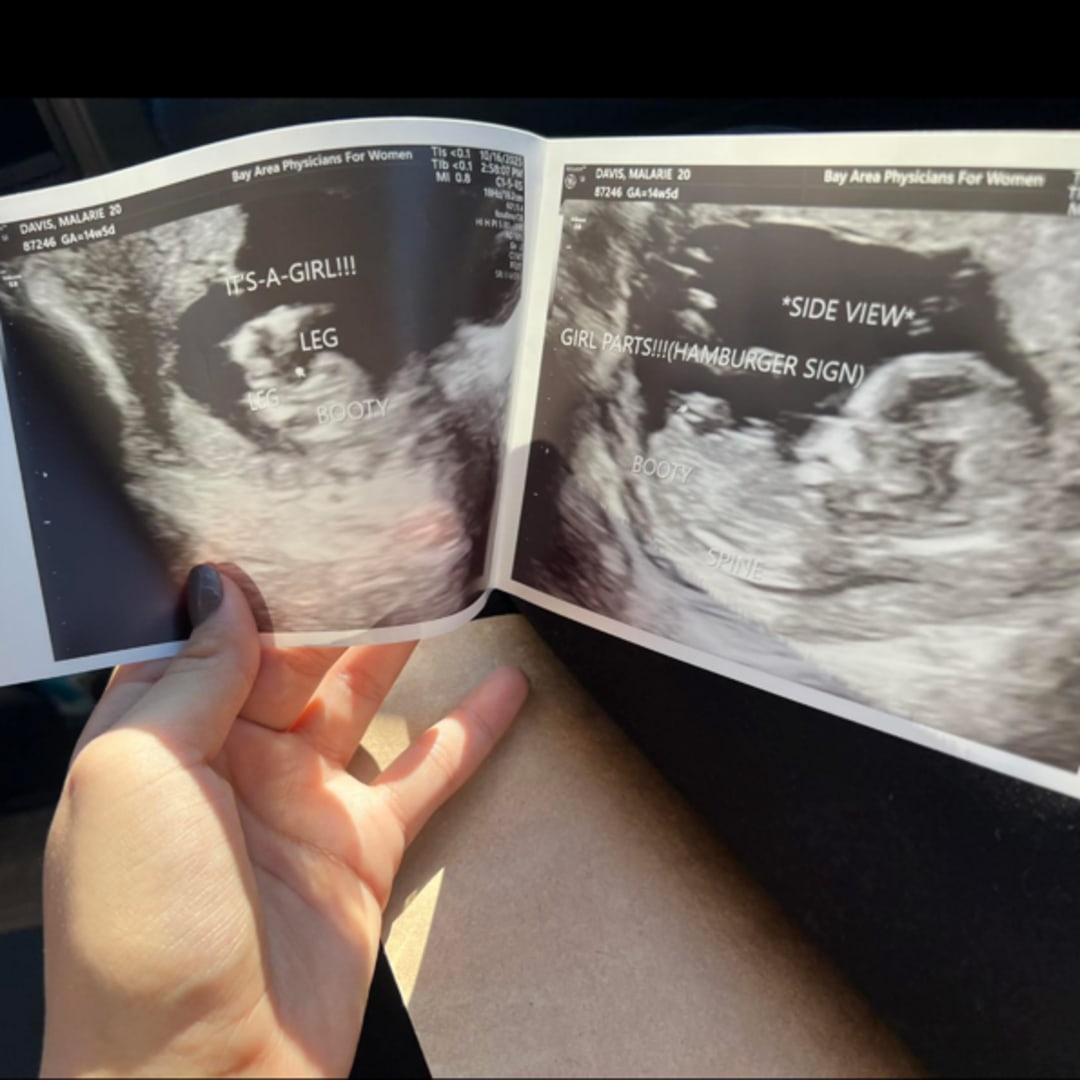

Matthew and I are so excited to welcome our sweet Aubrey Rose McIntosh in April 2026! 💕 We’ve put together a baby registry, and anything you’d like to contribute would mean the world to us.